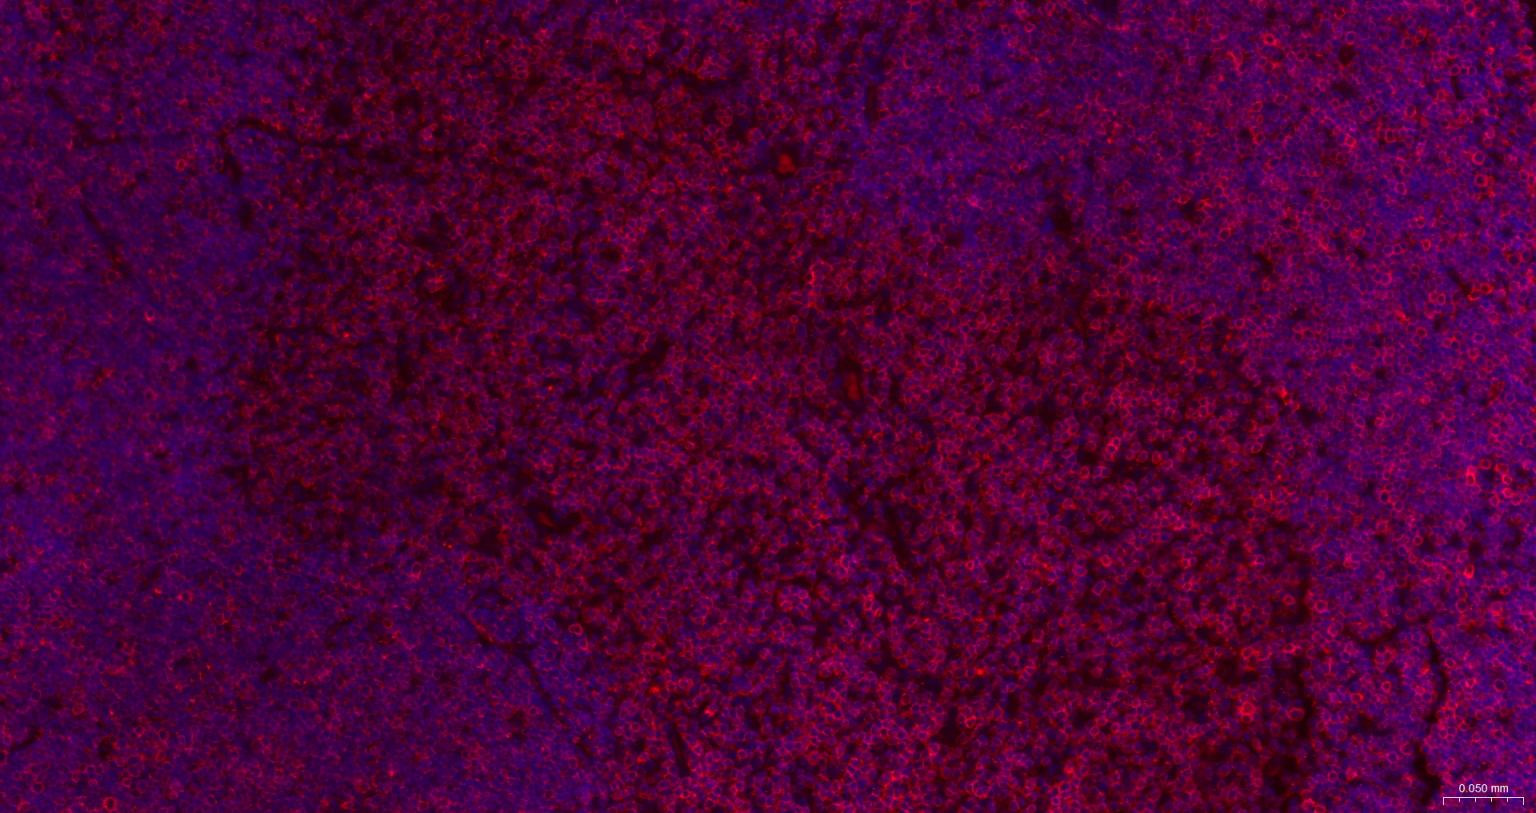

IHC-FHuman, Mouse, Rat1:500-2000

IFHuman, Mouse, Rat1:500-2000